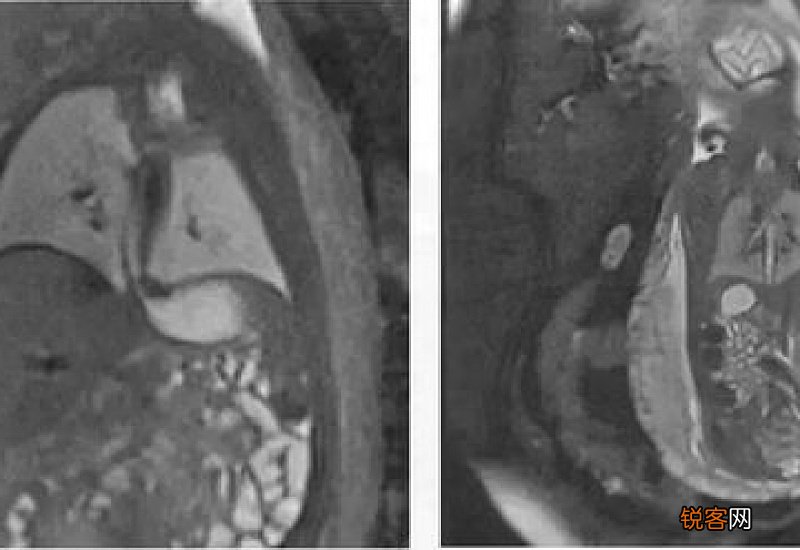

3. 核磁共振应用:核磁共振成像(MRI)检查已经成为一种常见的影像检查方式,核磁共振成像作为一种新型的影像检查技术,不会对人体健康有影响,但六类人群不适宜进行核磁共振检查即:安装心脏起搏器的人、有或疑有眼球内金属异物的人、动脉瘤银夹结扎术的人、体内物存留或金属假体的人、有生命危险的危重病人、幽闭恐惧症患者等 。